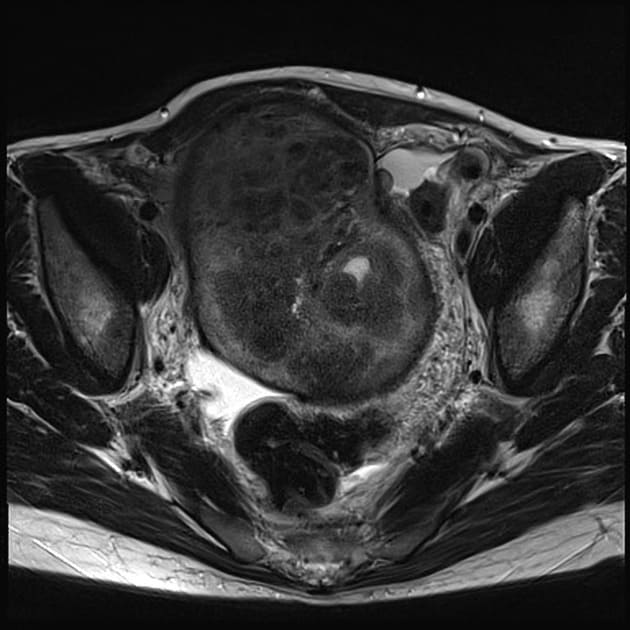

МРТ малого таза (полное название магнитно-резонансная томография) — это детальное, неинвазивное сканирование мочеполовой системы женщины и мужчины. По своей безопасности и безвредности она сопоставима с ультразвуковым сканированием, однако информационная точность и ценность данного обследования в разы выше.

Как делают МРТ органов малого таза у мужчин

Томография области малого таза у мужчин может проходить двумя способами:

- внеполосное — это когда МРТ катушка ставится сверху на область исследования, и пациент завозится внутрь томографа. Метод неинвазивный и не причиняет никаких неприятных ощущений.

- внутреннее – здесь используется специальная эндоректальная катушка, которая вводится в прямую кишку. Этот метод обладает наибольшей разрешающей способностью, но у чувствительных мужчин может вызвать легкий дискомфорт. В ходе ректального МРТ органов малого таза снижается расстояние между МРТ катушкой и приемником, что всегда улучшает качество получаемых снимков.